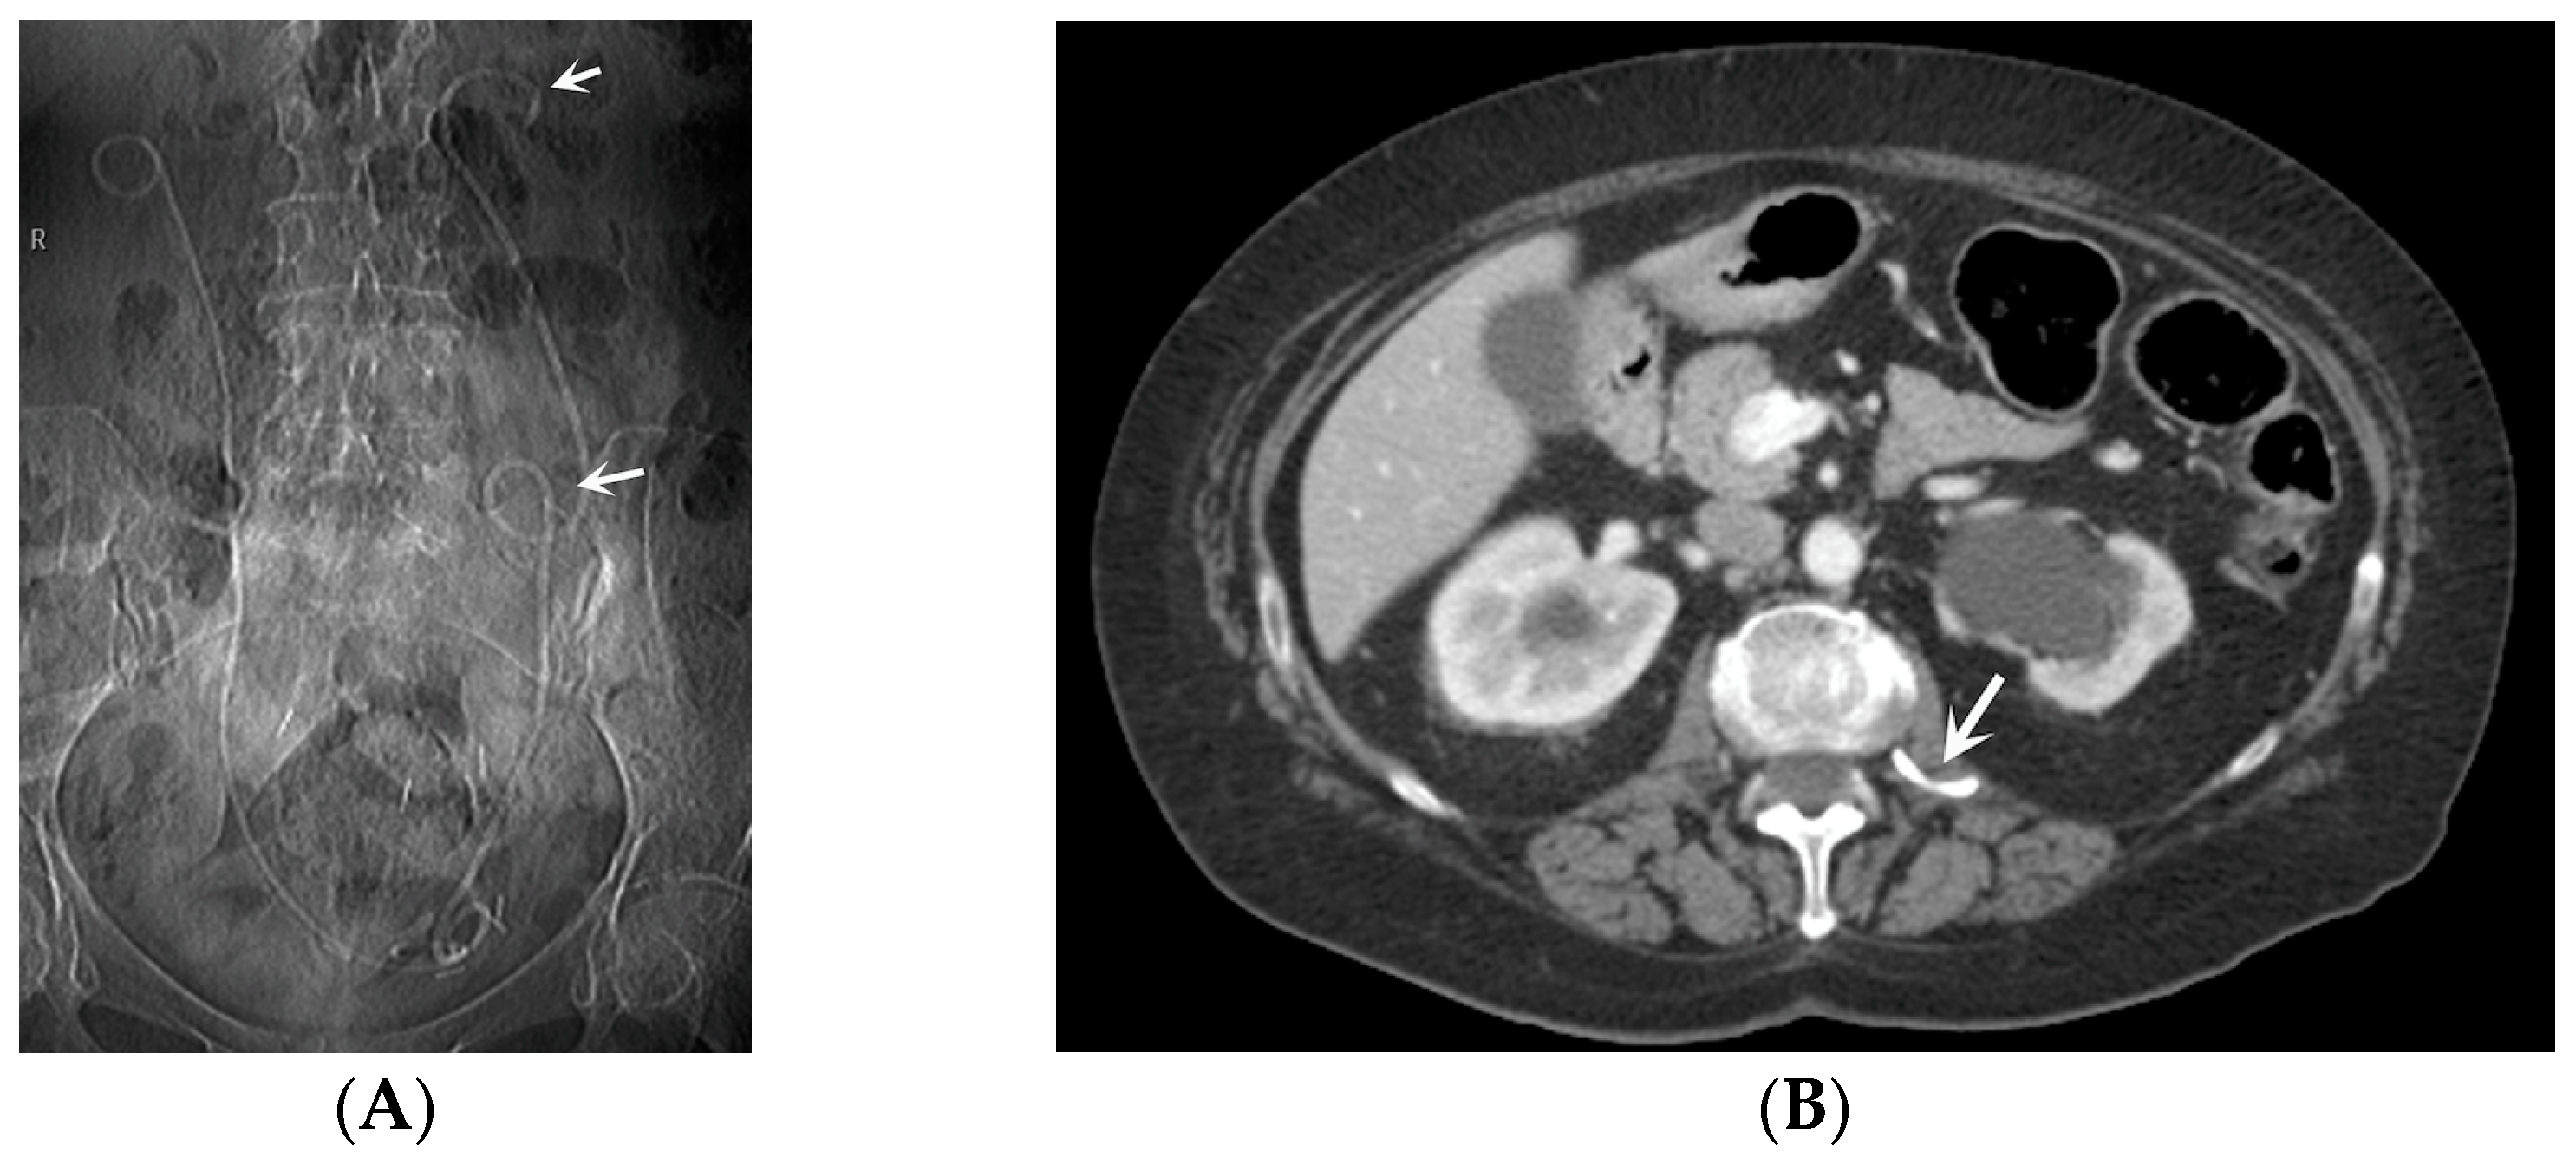

- Stent Knotting: It is a rare complication. Most of these knots involve the proximal end of the stent near the coil, but every portion can be affected [27,28]. Previous reports have attributed knot formation to the excessive length of the stent, stent shape (double-J or multicoil), and flexibility or anatomical abnormalities, such as cystocele and ileal conduits. An abdominal X-ray and, especially, a CT scan are more sensitive than other imaging modalities in identifying a ruptured or knotted stent as well as its migration (Figure 7) [29,30].